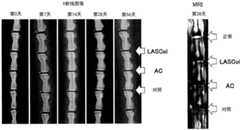

图10是进行了椎骨间距的维持试验的大鼠尾部的X光照片(图10(a))和MRI的T2加权像的照片(图10(b))。FIG. 10 is an X-ray photograph ( FIG. 10( a )) and a photograph of a T2-weighted image of MRI ( FIG. 10( b )) of the tail of the rat subjected to the vertebral distance maintenance test.

图10例示单纯X射线照片(图10(a))和术后4周的MRI(核磁共振成像,MagneticResonance Imaging)的T2加权像(图10(b))。图10(a)是术后的各经过天数的单纯X射线照片。箭头表示LASCol(第8、第9节尾椎骨间)、端胶原(记作“AC”;第9、第10节尾椎骨间)和对照(记作“对照”;第10、第11节尾椎骨间)的给药部位。FIG. 10 illustrates a simple X-ray photograph ( FIG. 10( a )) and a T2-weighted image of MRI (Magnetic Resonance Imaging) at 4 weeks postoperatively ( FIG. 10( b )). Fig. 10(a) is a simple X-ray photograph for each post-operative day. Arrows indicate LASCol (between

参照图10(b)。MRI的T2加权像中,LASCol给药组、AC给药组、对照组均比正常椎间盘(图10(b)中记作“正常”)的亮度低。但是,LASCol给药组与AC给药组和对照组相比亮度高。因此可以说,在除去髓核后,LASCol给药组与AC给药组、对照组相比退变减轻。Refer to Fig. 10(b). In the T2-weighted image of MRI, the luminance of the LASCol-administered group, the AC-administered group, and the control group was lower than that of the normal intervertebral disc (represented as "normal" in Fig. 10(b) ). However, the brightness of the LASCol-administered group was higher than that of the AC-administered group and the control group. Therefore, it can be said that the degeneration of the LASCol-administered group was less than that of the AC-administered group and the control group after the nucleus pulposus was removed.